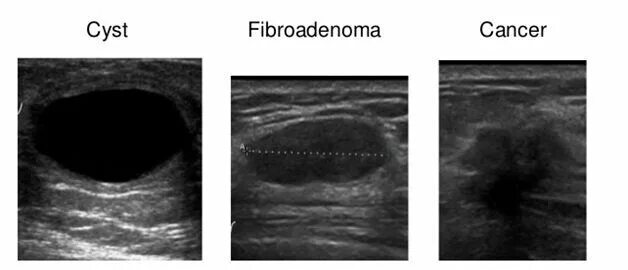

Как выглядит фиброаденома молочной железы